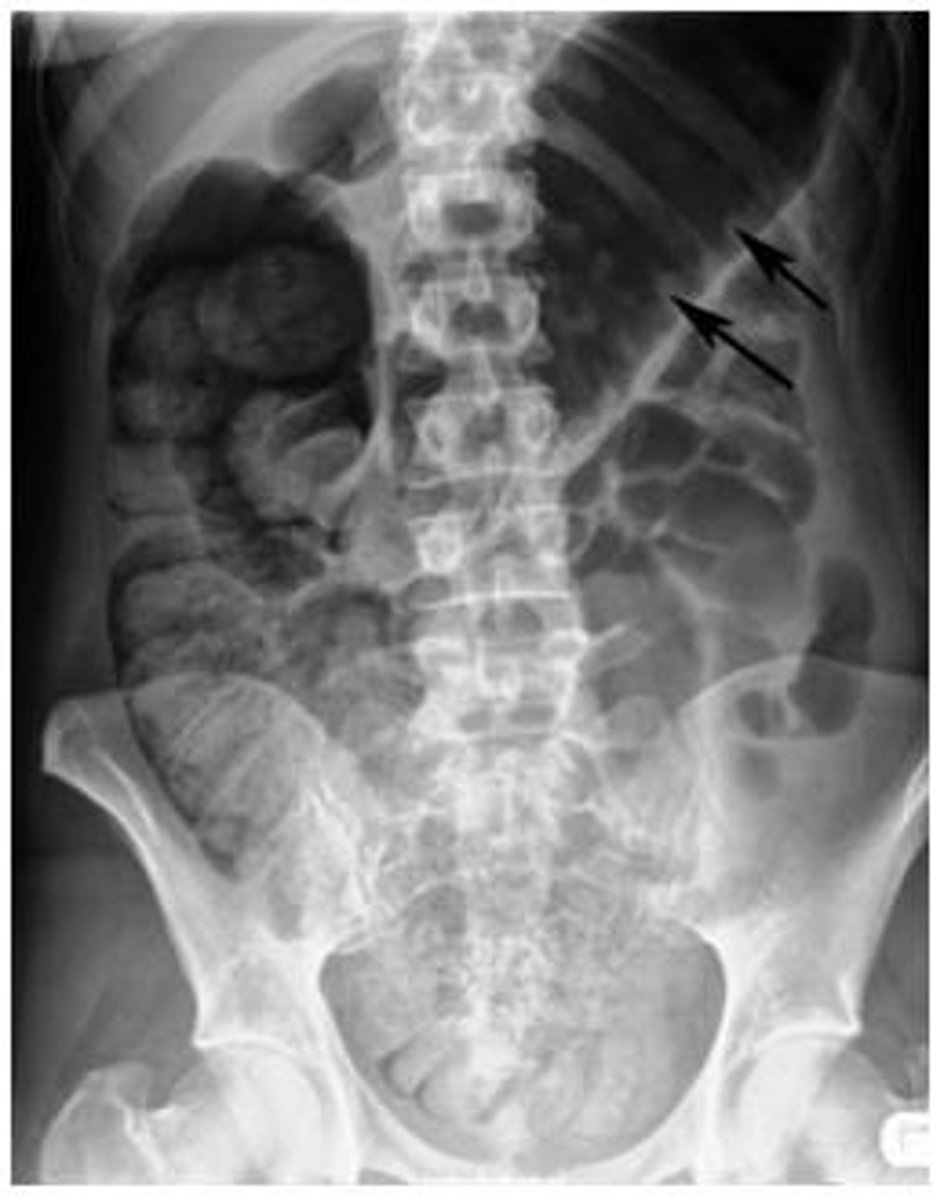

Suspect ___ in pts who have evidence of atherosclerotic vascular dz, present with abd pain followed by bloody diarrhea, and have minimal abdominal exam findings.

Ischemic colitis

- Splenic flexure most common (supplied by end arteries)

- vulnerable to ischemia during systemic hypotension in "water-shed" areas

- X-ray show "thumb printing"